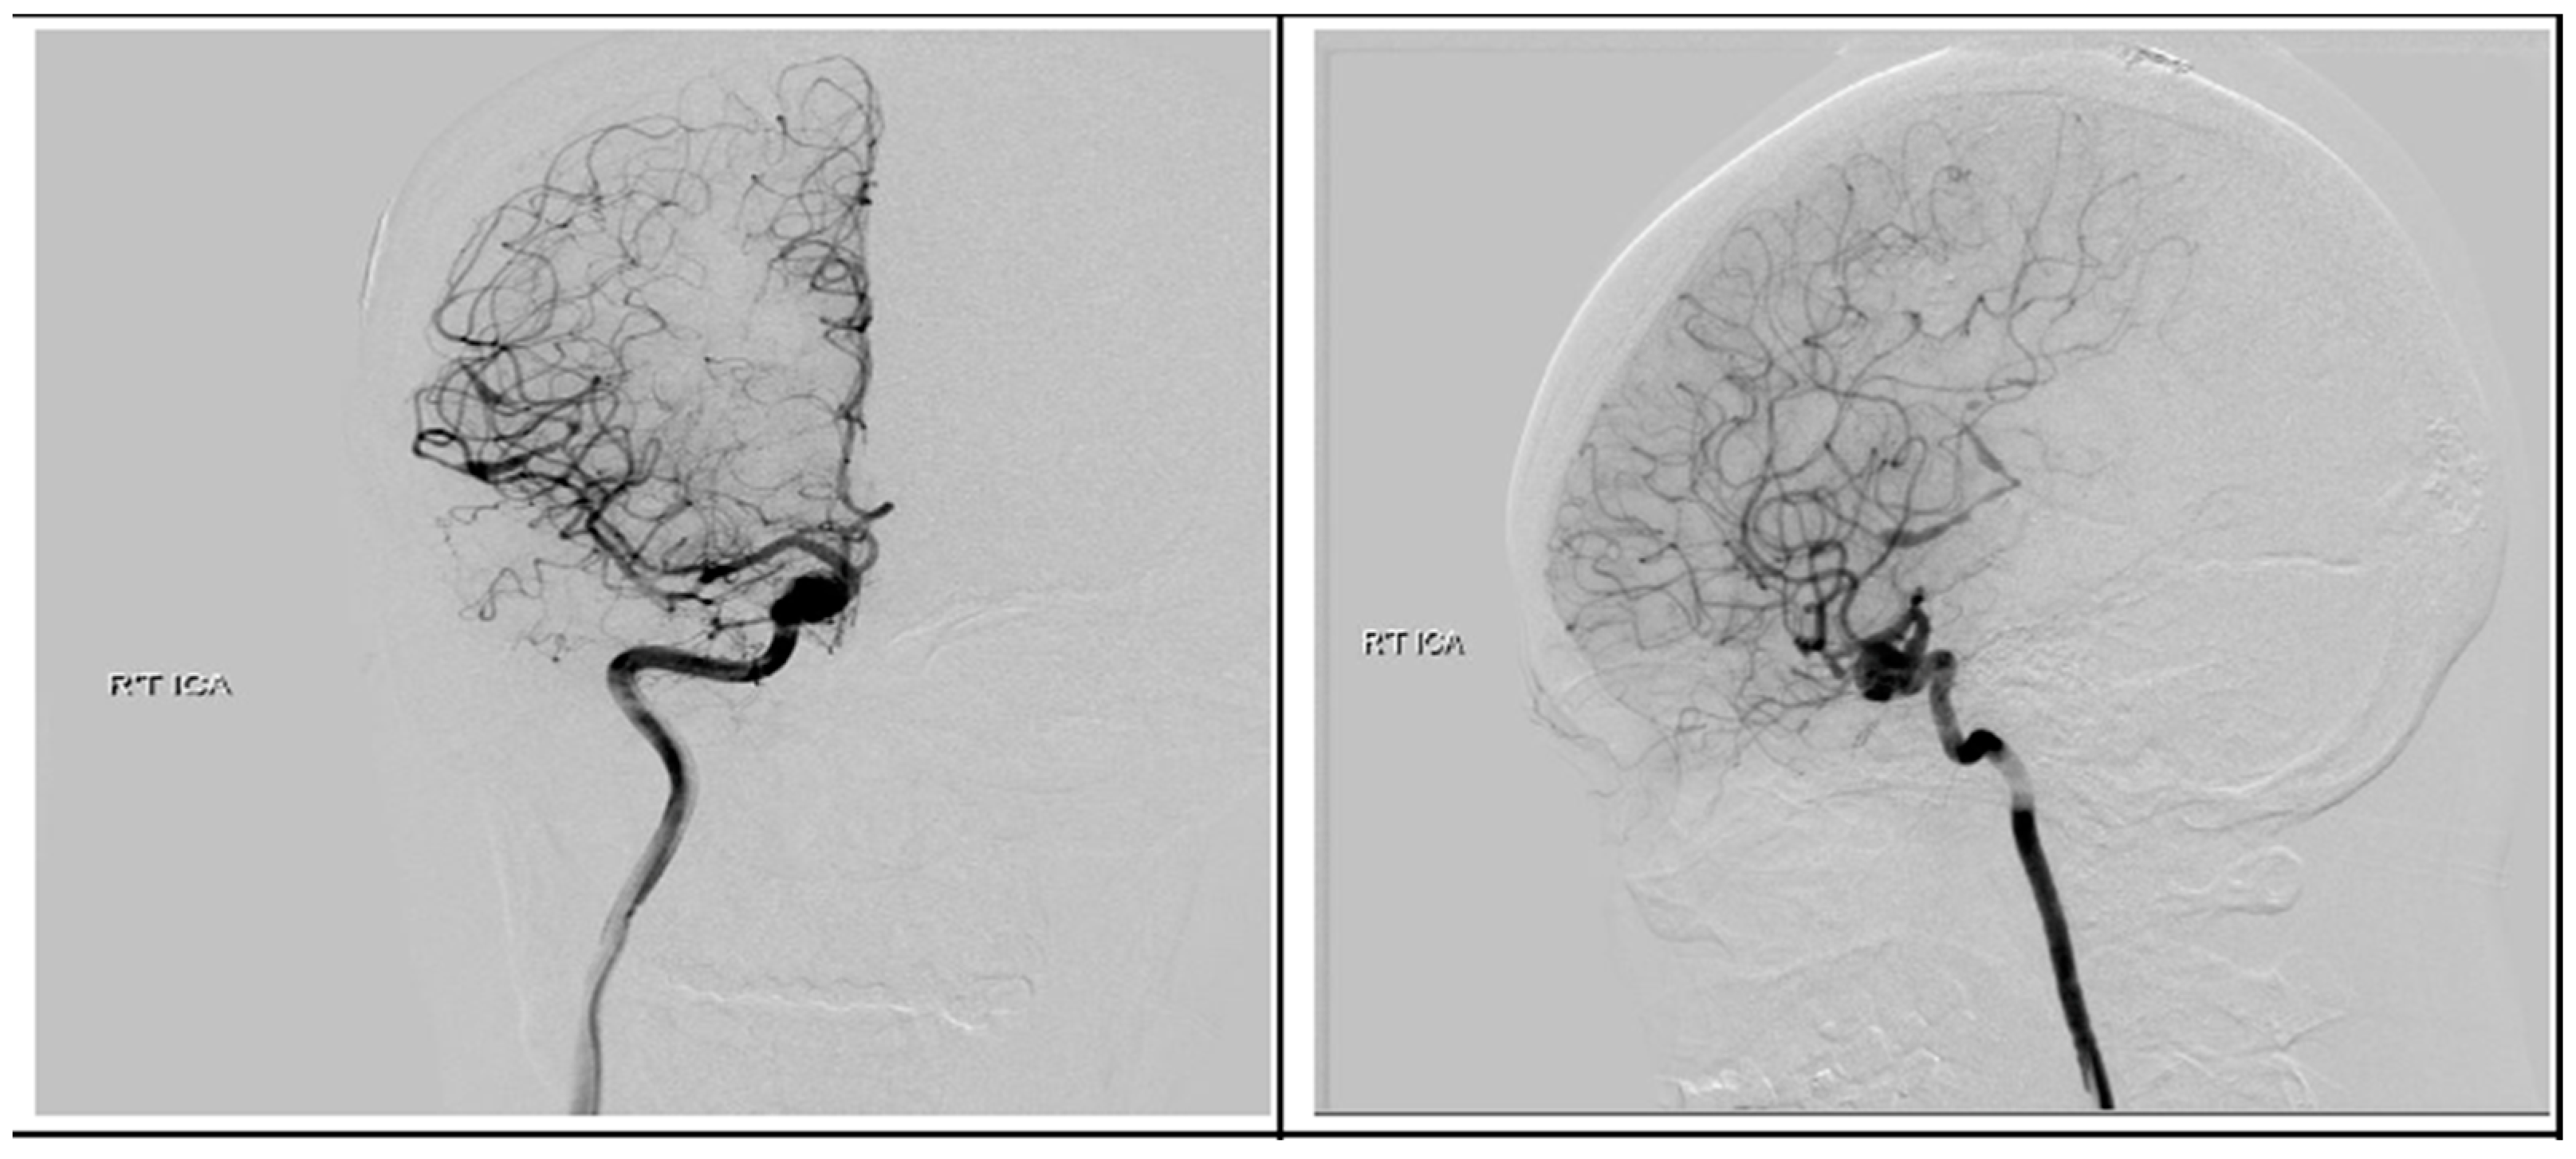

Following discharge, she underwent concurrent chemoradiotherapy with a total dose of 6900 cGy given in 30 fractions in conjunction with temozolomide (TMZ) at 75 mg/m2 daily. Upon a follow-up visitation 6 months post-operation, apart from previous neurologic deficits, she remained in good condition. Surveillance imaging showed no disease progression in the past 18 months after the surgery. We performed digital subtraction angiography (DSA) 4 months later and found no evidence of AVM, but the ICA aneurysm revealed only a sparse change in size without a sign of rupture Figure 9. After a detailed discussion with the patient and her family members, they decided to treat the aneurysm with endovascular intervention.

Figure 9.

Postoperative digital subtraction angiography. Angiography revealed a right supraclinoid internal carotid artery aneurysm.